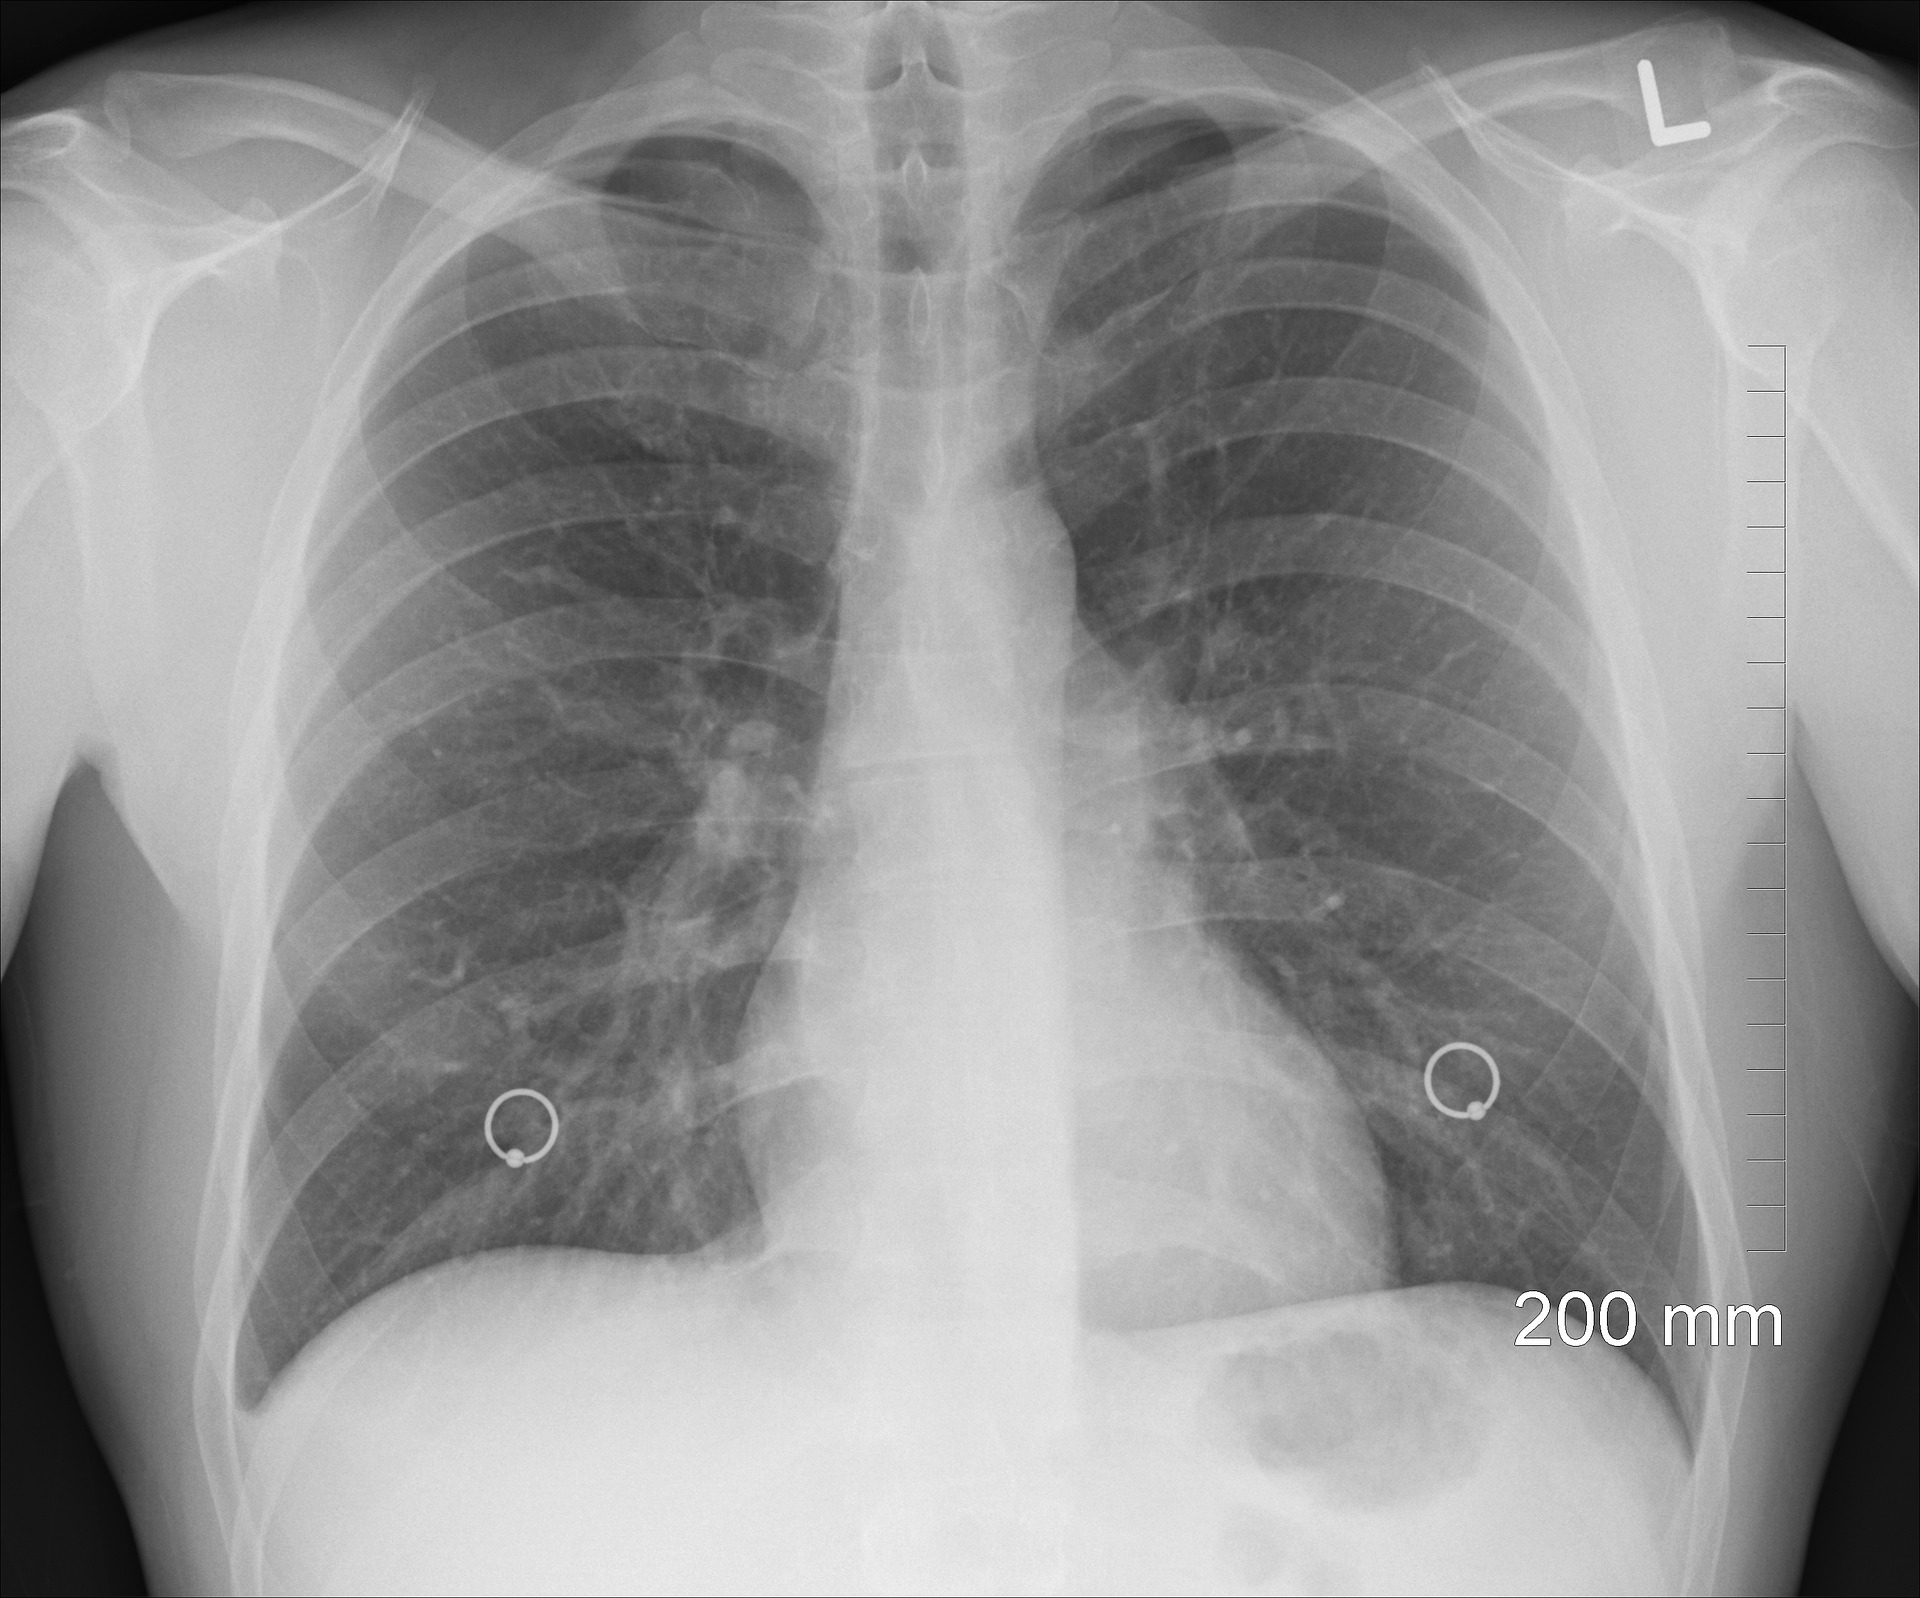

기도 부분에 자극으로 기침, 호흡 곤란이 발생할 수 있으며 혹시나 천식과 같은 기저질환이 있는 환자들은 악화될 수 있으며 부정맥까지 유발할 수 있다. 마스크 미착용으로 장시간 노출되면 폐기능 감소와 만성 기관지염으로 발전할 수 있다.

기도와 폐에서 박테리아를 불활성 화하여 제거하는 인체 방어 작용을 방해함으로써 호흡기 감염을 심화하며 심혈관질환에는 산화스트레스 염증 반응, 자율신경계의 혈액 응고 능력의 변의까지 될 수 있는 위험한 미세먼지입니다.